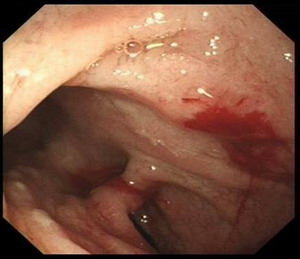

胃镜检查:反流性食管炎A级

萎缩性胃炎

十二指肠黏膜结节不平原因待查

十二指肠降段巨大憩室

胃镜影象